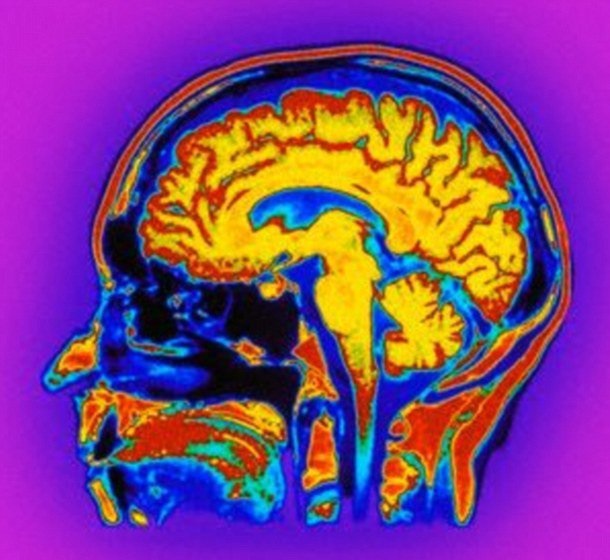

در گام بعدی این بیمار تحت سیتیاسکن مغز قرار گرفت و پزشکان تصمیم گرفتند برای آرام نگهداشتن وی به او داروی رایج ضد اضطراب میدازولام را بدهند. اما در نهایت تعجب، SV بیدار شده و با پزشکان و خانوادهاش شروع به صحبت کرد. اگرچه وی چیزی در مورد تصادف و شرایطش تا پس از بازگشت به هوشیاری کامل به یاد نمیآورد.

دو ساعت بعد که اثر دارو از بین رفت، بیمار مذکور مجددا به حالت پیشین با کمترین هوشیاری بازگشت. پزشکان چند هفته بعد مجددا به SV داروی میدازولام دادند و اینبار رفتار و خوانشهای نوار مغزی وی را مورد بررسی قرار دادند. بررسیها نشان داد که مصرف این دارو باعث تغییر در فعالیت امواج مغزی در دو ناحیه مغز بیمار میشد.

بخش اول مغز موسوم به شبکه کار مثبت است که به انسان در واکنش به وظایفی کمک میکند که نیازمند توجه فرد است.

بخش دومی مشئول تکلم و فهم زبان است.